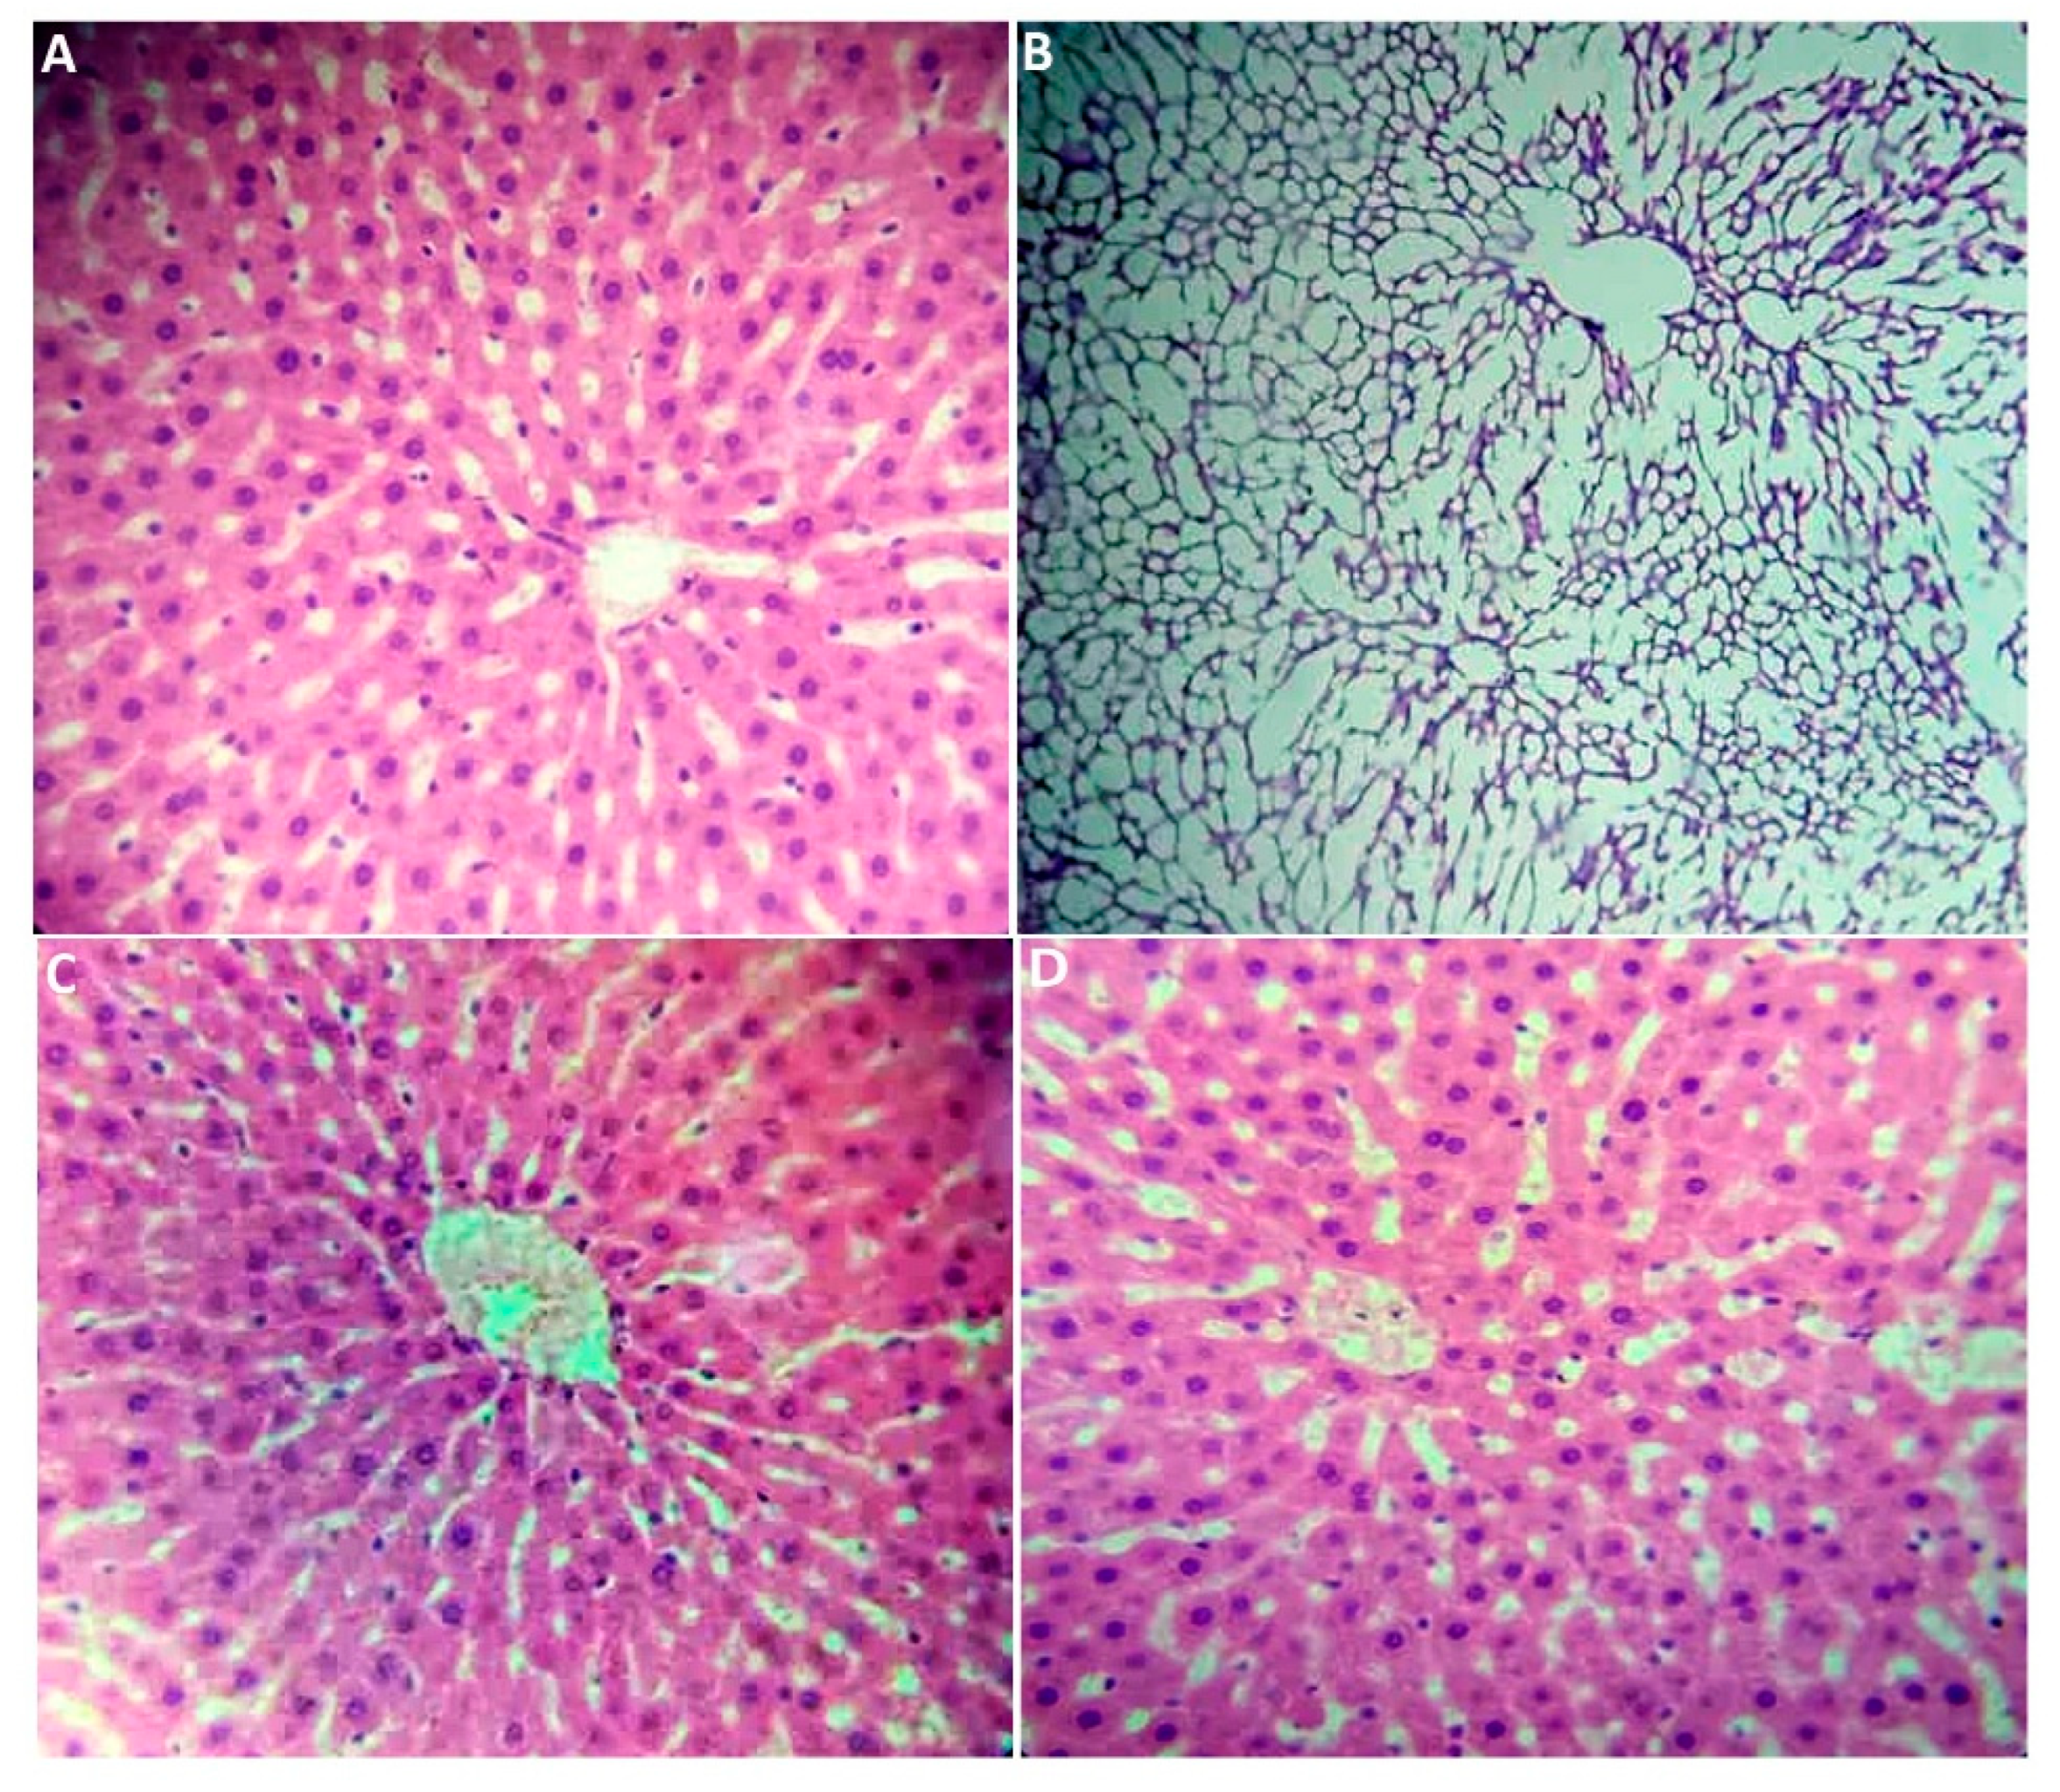

2.2.7. Histological Section Study